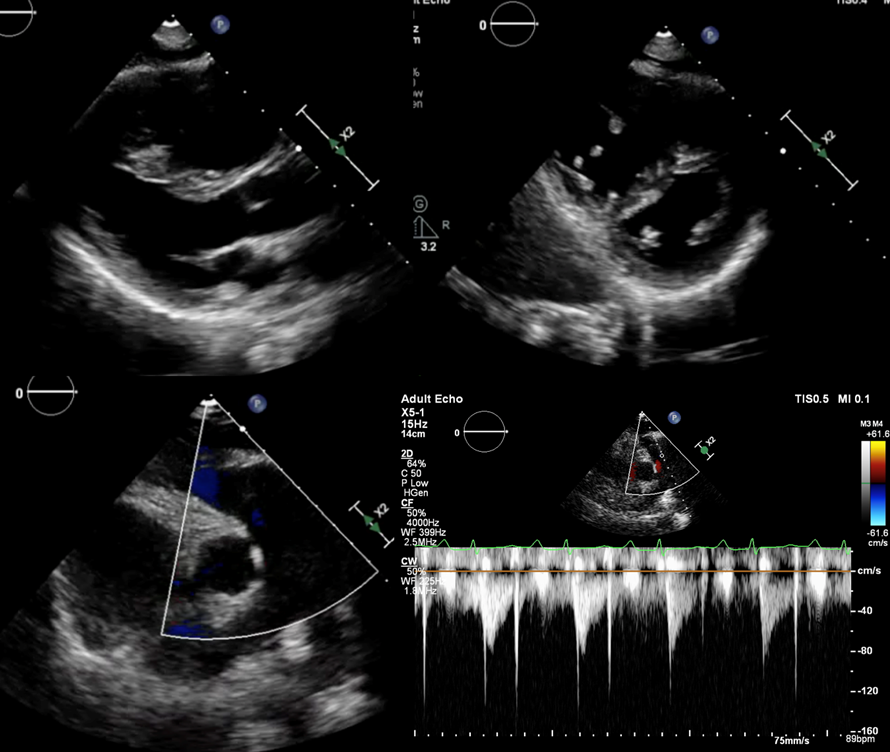

SaÄŸ kalp boÅŸluklarında dilatasyon saptanan hastanın saÄŸ atriyum (RA) alanı: 22.5 cm². TAPSE ve S ’ dalgası azalmış olan hastada, triküspit yetersizliÄŸi ileri olarak deÄŸerlendirildi ve TY velositesi 4.3 m/s ölçüldü. İnferiyor vena kava (IVC): 25 mm olup, solunumla ile kollabe olmamaktaydı. sPAP: 75 + 15 = 90 mmHg olarak hesaplandı (Åžekil 3.). Transözofageal ekokardiyografide intrakardiyak ÅŸant saptanmazken, tüm pulmoner venlerin sol atriyuma döküldüğü görüldü.

Åžekil 3.